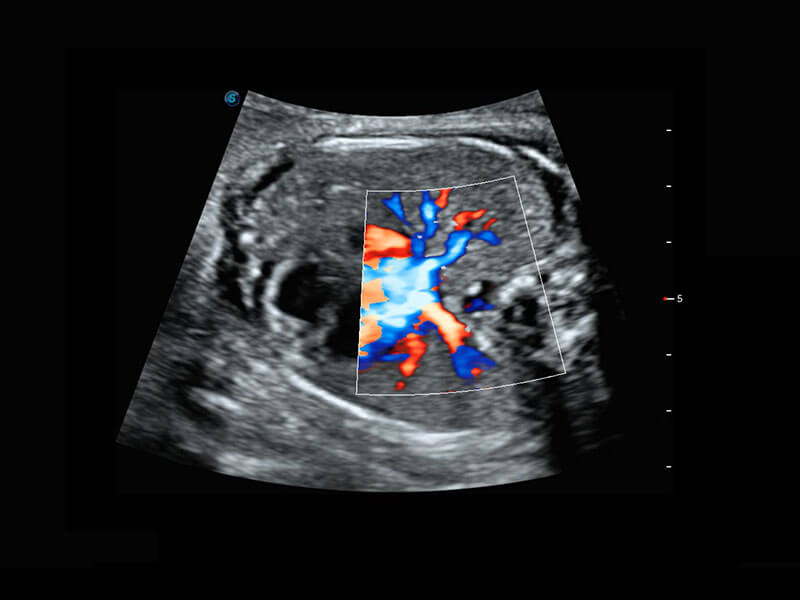

四腔心血流

右室双出口